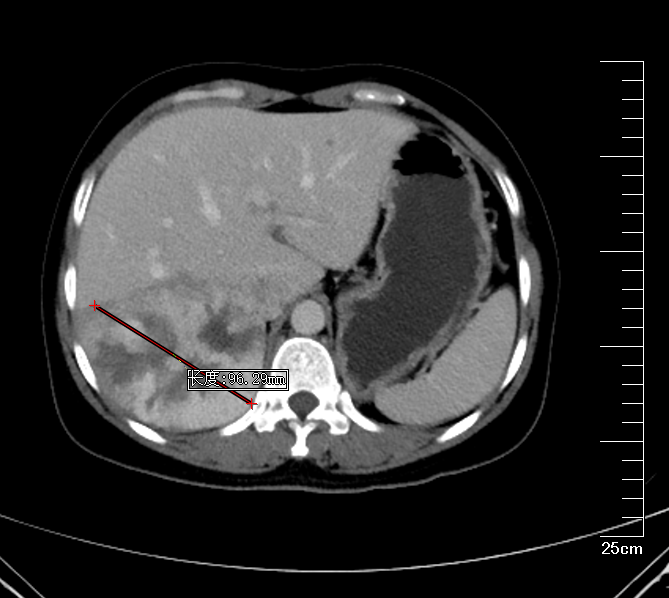

肝右叶巨大血管瘤MRI

肝胆胰外科古松钢副主任在查看患者及外院CT报告后,认为患者右肝巨大肿物,大小约9*10*9.5cm,考虑为肝右后叶巨大血管瘤,需积极行手术治疗,否则血管瘤有破裂出血可能。将钱女士收治入院后,进一步完善腹部增强CT,评估患者肝储备功能以及心肺功能。